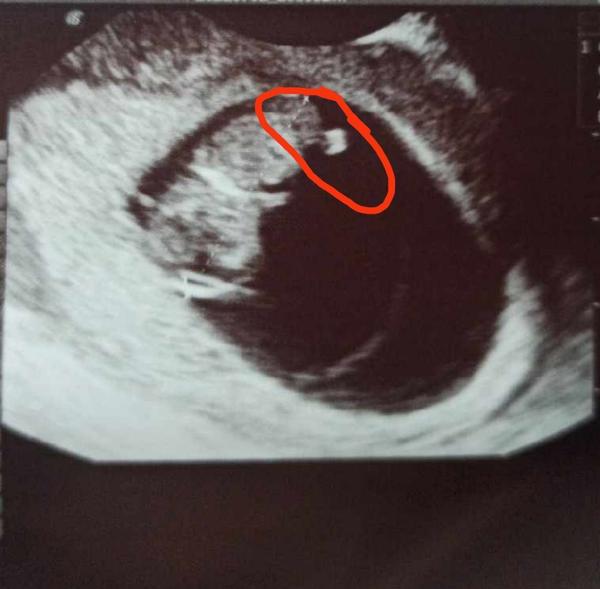

Co může znamenat nález na ultrazvuku 9+3?

Ahojky všem, chtěla bych se zeptat zda-li někdo náhodou netušíte co by to mohlo být u té hlavičky na ultrazvuku, fotografii jsem si prohlédla pořádně az doma takže jsem neměla možnost se zeptat lékaře, chápu že zde nejsou doktoři atd.. Jen by mne zajímalo jestli by někdo náhodou nevěděl co to může být

V 9 tt spíš zbytek žloutkového váčku, než placenta. Kazdopádně je to "servisní tkáň" mimo tělo plodu.

Pokud myslíte to v tom kolečku tak bych řekla pupeční šnura nebo placenta ,hlavička je dole ne?